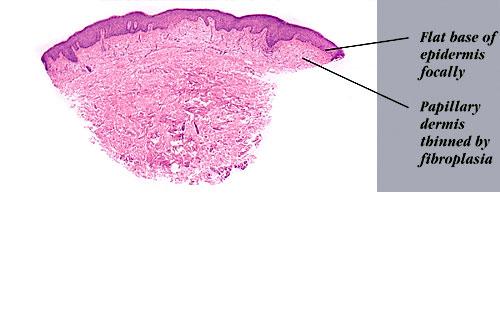

Erythema elevatum diutinum = الحمامى المرتفعة الدائمة Erythema Elevatum Diutinum This rare condition is characterized by persistent, initially red to violaceous and later brown to yellow papules, nodules, and plaques . The lesions, typically distributed symmetrically on the extensor surfaces of the extremities, are initially soft and then evolve into fibrous nodules. Histopathologic Features. In […]